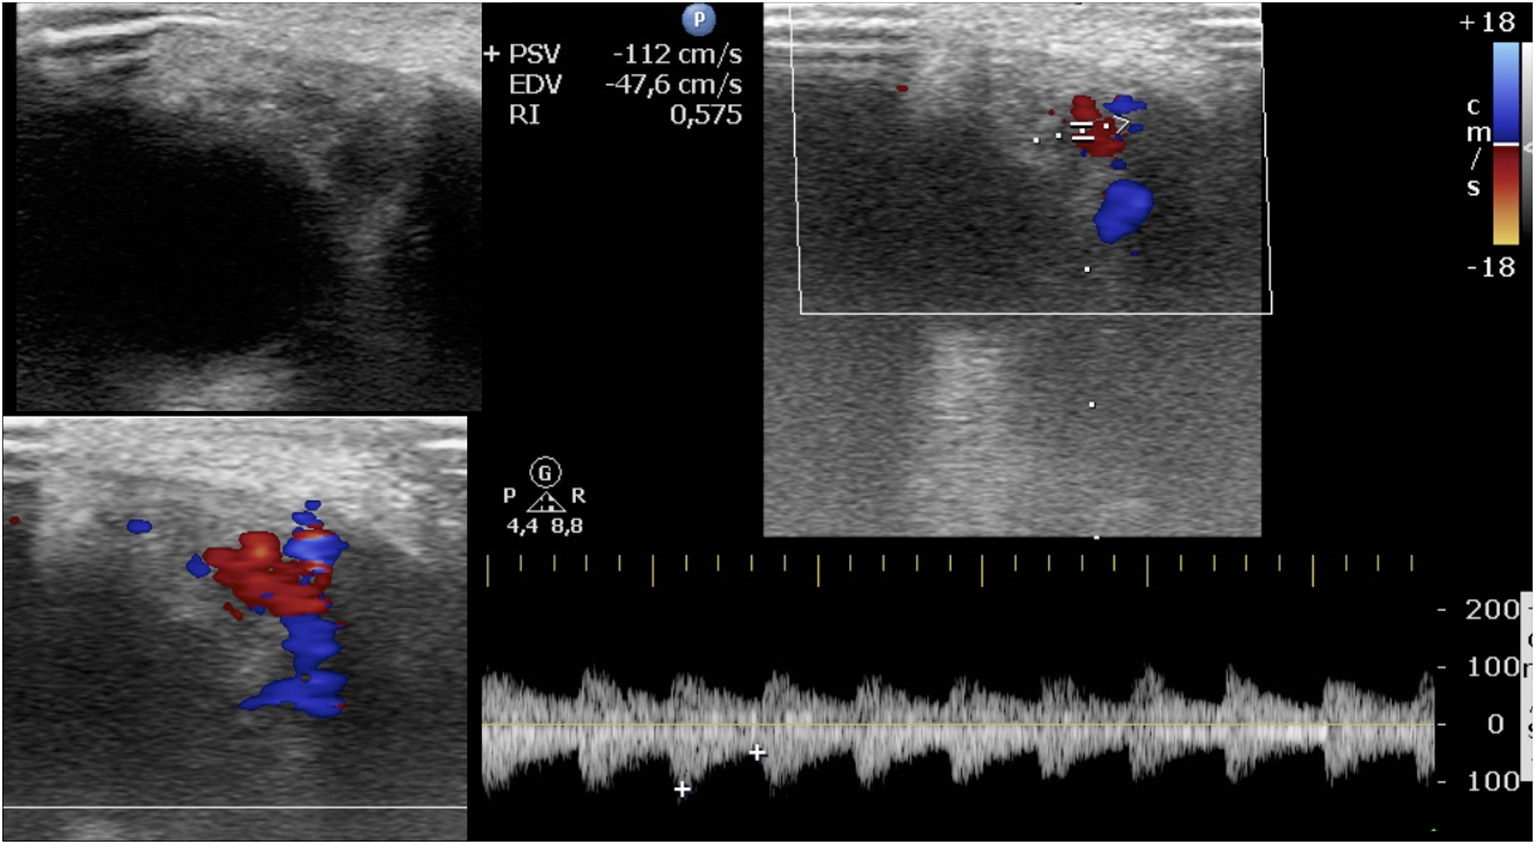

FIGURE 1

www.frontiersin.org

Figure 1. Periorbital infantile hemangioma. Baseline ultrasound images show a circumscribed mostly hypoechoic mass; at color Doppler, the lesion is highly vascularized, and the resistive index is 0.59.

A total of 64 IHs in 60 patients were retrospectively analyzed. Four children had two IHs. All IHs had a good clinical response to oral propranolol. A good clinical result is defined as a complete or almost complete or partial regression of IH. The infants were 19 male and 41 female. The age at diagnosis was between 0.9 and 8.3 months, with an average age at diagnosis of 3.5 months. The average age of initiation of treatment was 5 months (Tables 1, 2). Twenty out of 64 lesions were excluded from the evaluation of RI values because, at the ultrasound examination after 1 month of therapy, they did not show significant vascular signals for sampling. The RI values where then compared in 44 lesions with at least two significant samplings of RI and evaluated until the disappearance of the color Doppler signals. Among these 44 lesions, 24 were superficial IHs, 13 mixed his, and seven deep IHs. In 44 lesions, we recorded the values sampled in each IH and calculated the mean RI value. We compared the mean RI values at baseline with the mean RI values at the last control during treatment, in which it was possible to sample the vascular signals. The last ultrasound examination in which it was possible to detect and sample RI values was the evaluation at the first month after therapy in 14 lesions, at the third month of therapy in nine lesions, and at the sixth month of therapy in 21 lesions. In the 44 lesions compared, we did not find statistically significant variations in the mean RI values between the baseline control (0.57) and the values recorded at the last post-treatment control, in which there were appreciable vascular signals (0.58) (Table 3) (Figures 1, 2).